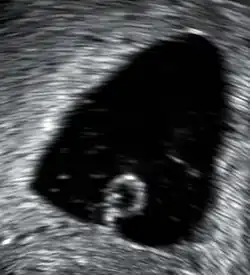

![]() | |

| An ultrasound showing a gestational sac containing a yolk sac but no embryo | |

In the case of blood loss, pain, or both, transvaginal ultrasound is performed. If a viable intrauterine pregnancy is not found with ultrasound, blood tests (serial βHCG tests) can be performed to rule out ectopic pregnancy, which is a life-threatening situation.[107][108]

A miscarriage may be confirmed by an obstetric ultrasound and by the examination of the passed tissue. When looking for microscopic pathologic symptoms, one looks for the products of conception. Microscopically, these include villi, trophoblast, fetal parts, and background gestational changes in the endometrium. When chromosomal abnormalities are found in more than one miscarriage, genetic testing of both parents may be done.[109]